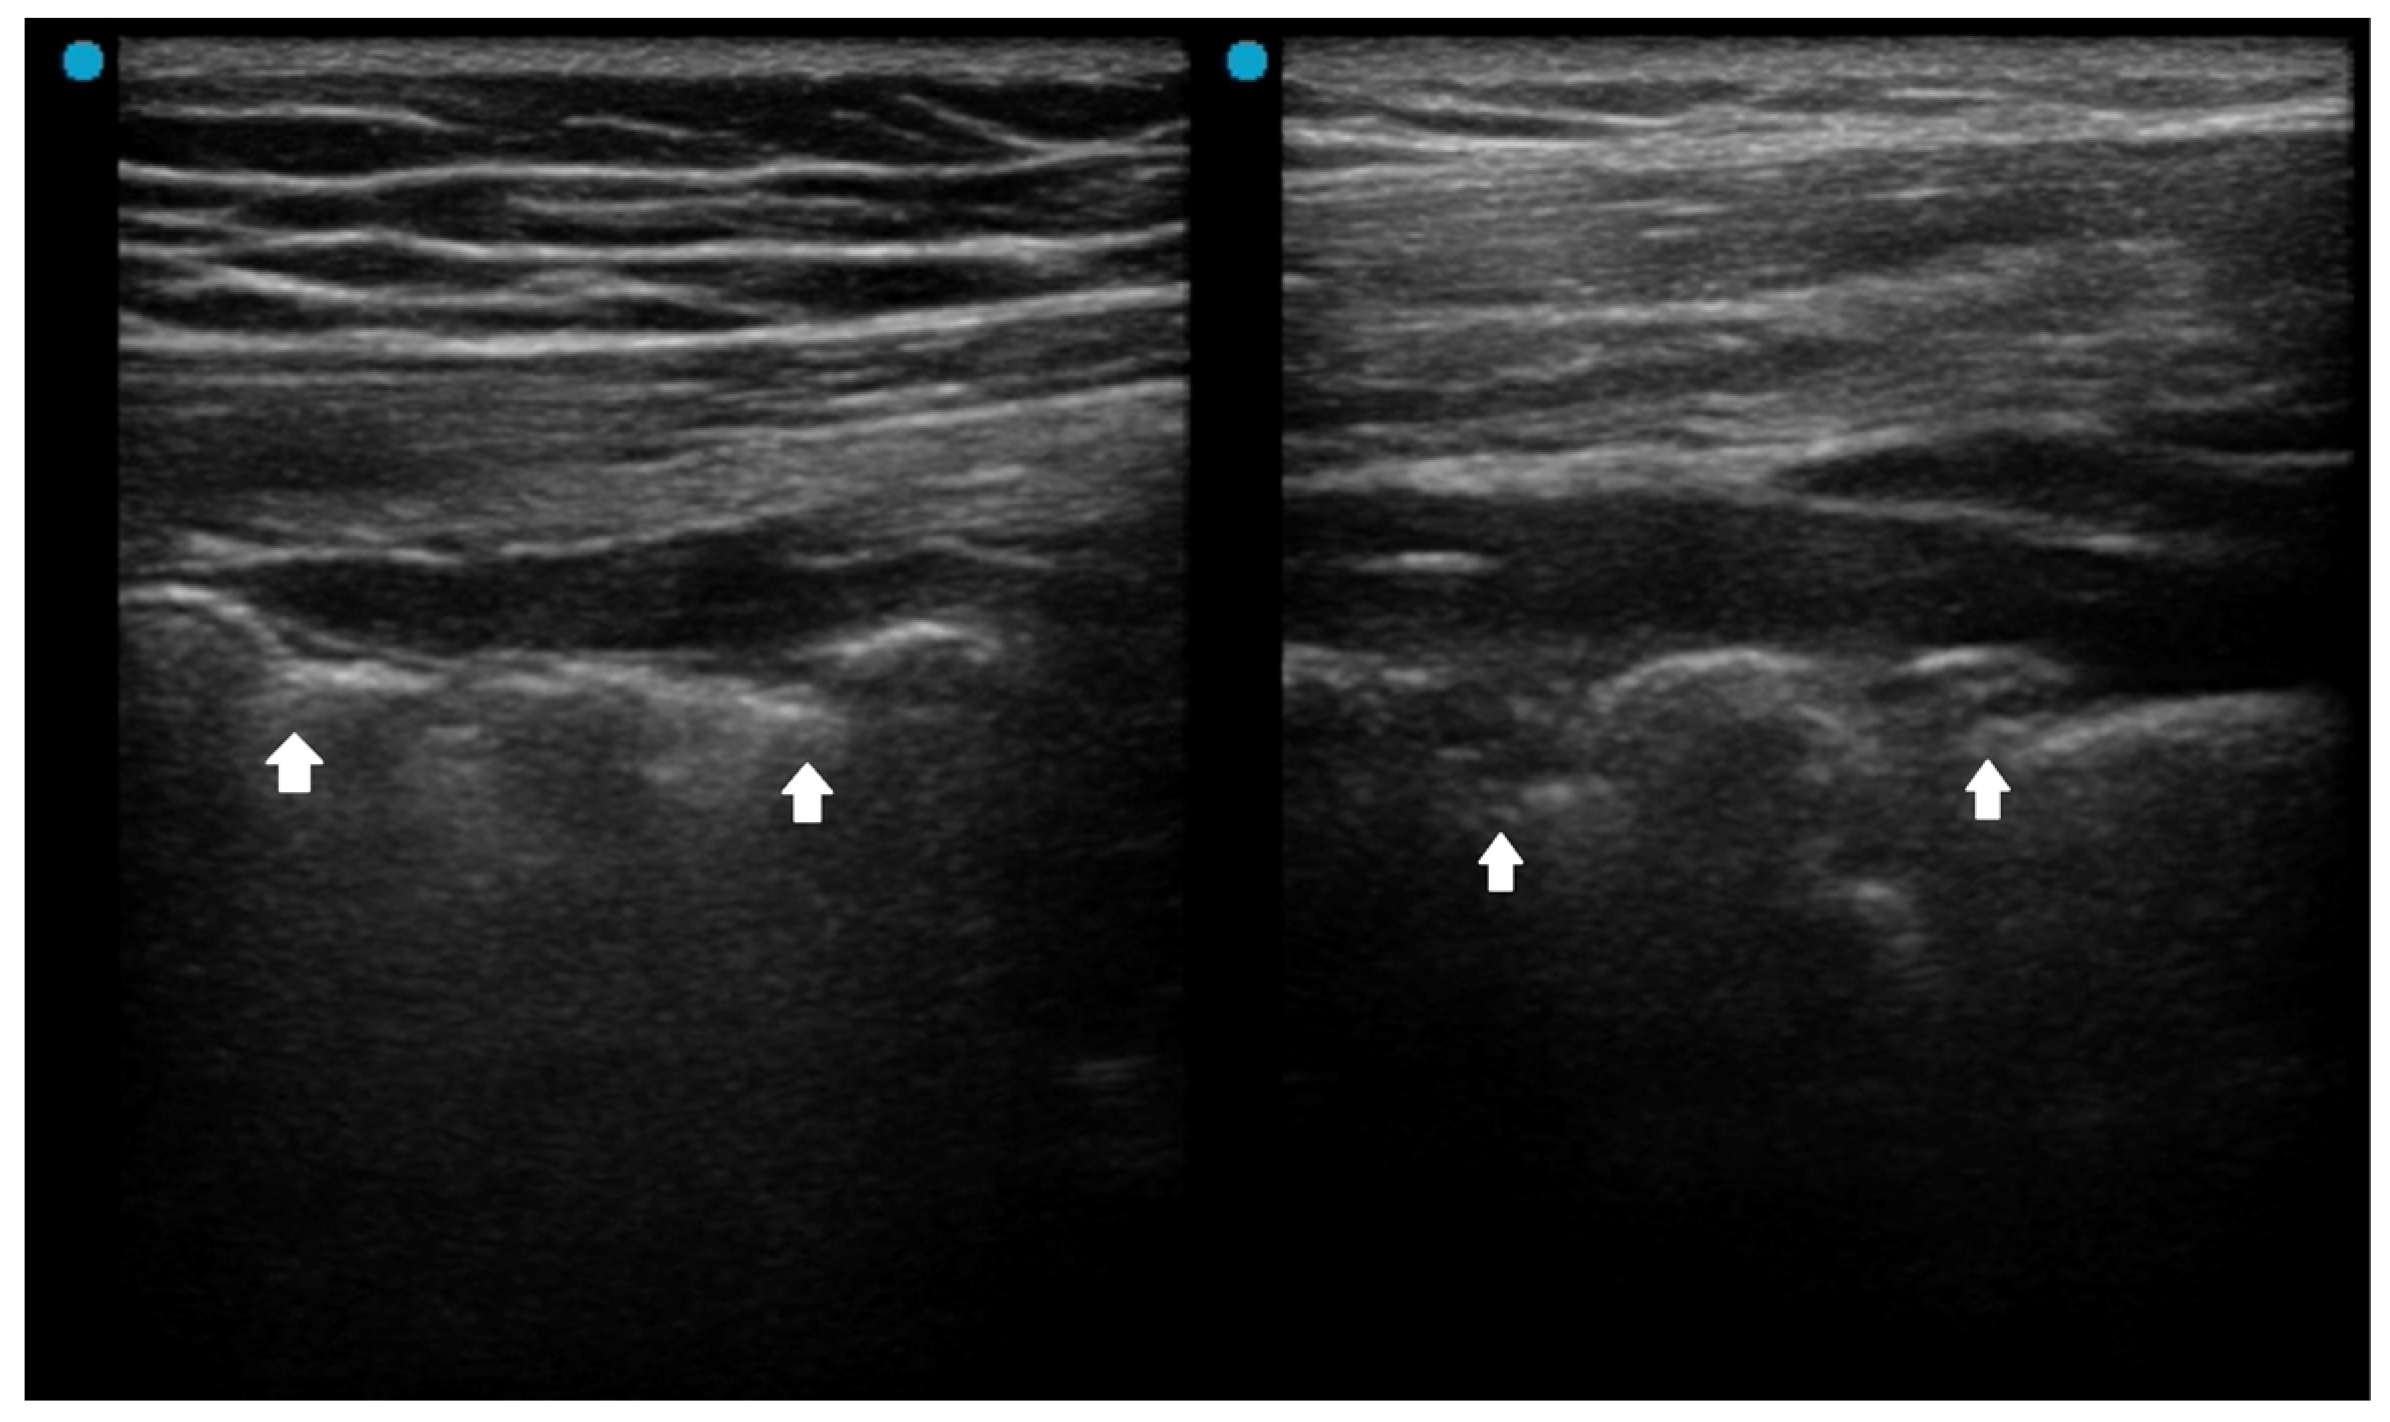

| Fluid (liquid) bronchogram | Post-obstructive pneumonia |